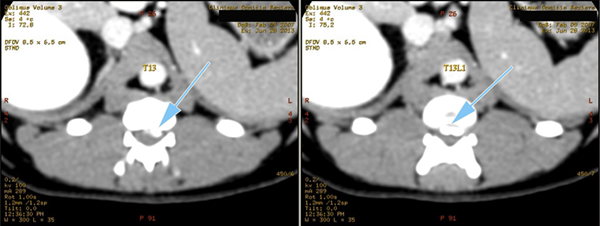

Le Scanner ou Tomodensitométrie Numérisée.

Depuis quelques années, le développement du scanner en médecine vétérinaire (imagerie par tomodensitométrie numérisée) s'est fortement accéléré avec la multiplication des structures équipées.

Le scanner est actuellement l'examen de choix pour le diagnostic des hernies discales chez les carnivores domestiques et d'une façon générale pour l'exploration des pathologies du rachis. Ses capacités de dessuperposition des structures anatomiques et sa meilleure résolution spatiale lui permettent, avec les machines de dernière génération, de supplanter définitivement les examens radiologiques sous contraste.

Le scanner permet à la fois une meilleure approche de l'étage de la lésion, mais aussi une meilleure latéralisation de celle-ci, ce qui est capital en cas de geste chirurgical. Il permet aussi, en cas de hernies multiples (ce qui est fréquent dans certaines races comme le Bouledogue français) d'avoir une approche lésionnelle permettant, au travers de critères objectifs, de faire un tri entre les hernies pour isoler celle responsable des symptômes nerveux.

L'examen tomodensitométrie du rachis se fait avant et après injection de produit de contraste iodé pour rehausser les lésions. Dans certains cas extrêmes, et au demeurant rarissimes, une injection complémentaire de produit de contraste dans l'espace sous arachnoïdien peut être nécessaire, l'examen réalisé alors se nomme un myéloscanner. Cet examen peut s'avérer très utile, notamment pour le diagnostic de certaines affections rares des méninges nommées kystes arachnoïdiens, présentes en particulier chez le Rottweiler, et dont le diagnostic constitue une des limites du scanner avec le syndrome de Chiari.

Coupes axiales

Scanner d'une Hernie discale T13L1 extrusive chez un chien reformatages sagittal et coronale